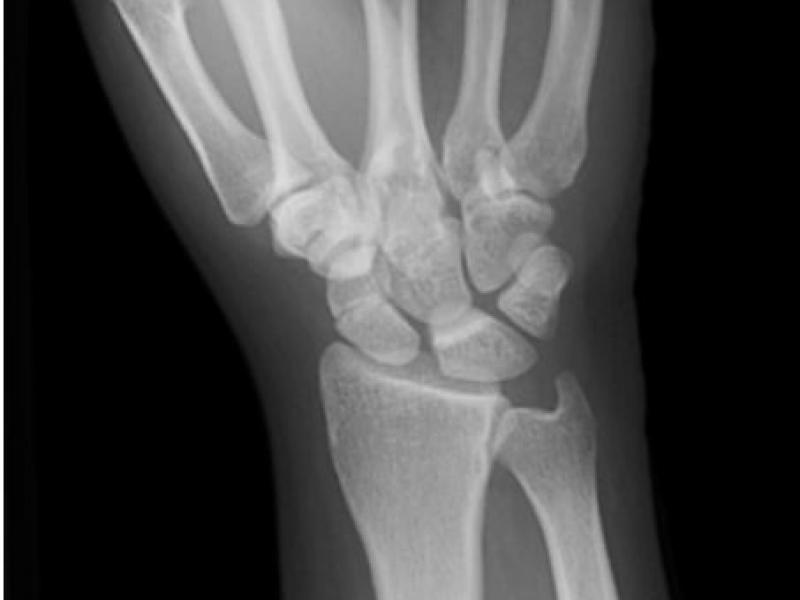

25 year-old female presents following a fall from her horse